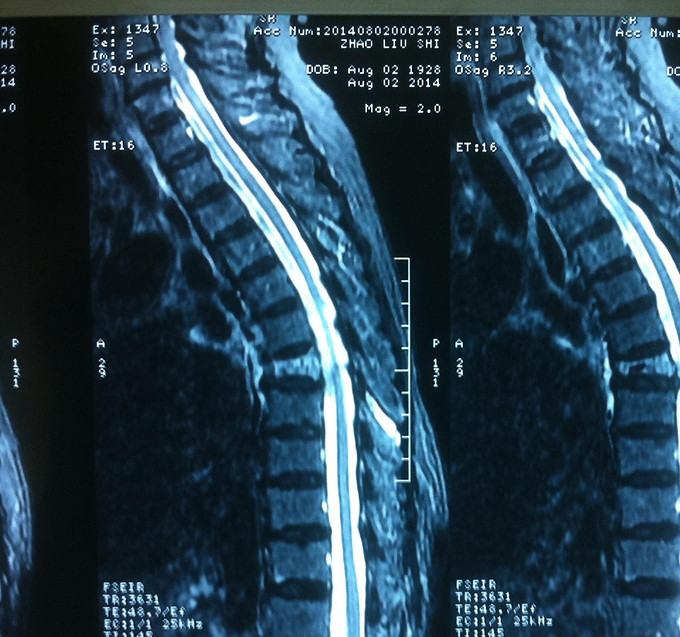

专科查体:背部后凸畸形,背部叩痛,腰骶部无叩痛,双下肢感觉无减退,双下肢肌力4-5级,双侧膝腱反射++,巴氏征阴性。影像学检查:X-Ray;骨质疏松、胸8楔形变。MR:胸8压缩性骨折,新鲜。